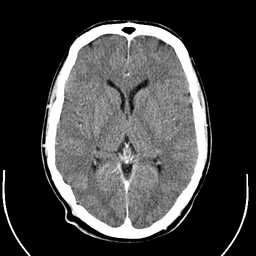

This thesis works to address a pivotal challenge in medical image analysis: the reliance on extensive labeled datasets, which are often limited due to the need for expert annotation and constrained by privacy and legal issues. By focusing on the development of self-supervised learning techniques and domain adaptation methods, this research aims to circumvent these limitations, presenting a novel approach to enhance the utility and efficacy of deep learning in medical imaging. Central to this thesis is the development of the Medformer, an innovative neural network architecture designed for multitask learning and deep domain adaptation. This model is adept at pre-training on diverse medical image datasets, handling varying sizes and modalities, and is equipped with a dynamic input-output adaptation mechanism. This enables efficient processing and integration of a wide range of medical image types, from 2D X-rays to complex 3D MRIs, thus mitigating the dependency on large labeled datasets. Further, the thesis explores the current state of self-supervised learning in medical imaging. It introduces novel pretext tasks that are capable of extracting meaningful information from unlabeled data, significantly advancing the model's interpretative abilities. This approach is validated through rigorous experimentation, including the use of the MedMNIST dataset, demonstrating the model's proficiency in learning generalized features applicable to various downstream tasks. In summary, this thesis contributes to the advancement of medical image analysis by offering a scalable, adaptable framework that reduces reliance on labeled data. It paves the way for more accurate, efficient diagnostic tools in healthcare, signifying a major step forward in the application of deep learning in medical imaging.💡 Deep Analysis